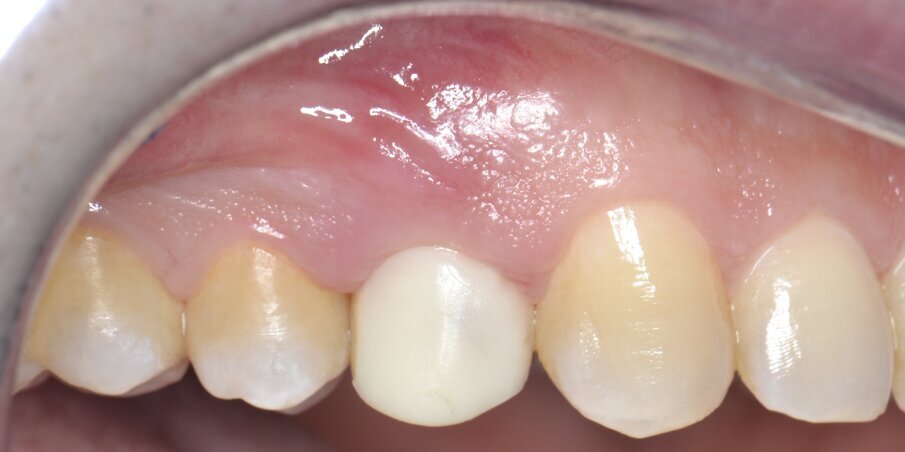

Il primo follow-up effettuato a 14 giorni mostra un eccellente stato di salute dei tessuti duri e molli; è importante sottolineare come il profilo di emergenza della protesi provvisoria, opportunamente lucidato al momento della protesizzazione, guiderà i tessuti molli durante tutto il periodo di guarigione (Fig. 19). Le immagini del secondo follow-up a 4 mesi indicano una condizione di sostanziale salute e stabilità dei tessuti peri-implantari duri e molli: questo consente di programmare la successiva fase di finalizzazione protesica (Fig. 20).

Fig. 19 - Follow-up a 14 giorni.